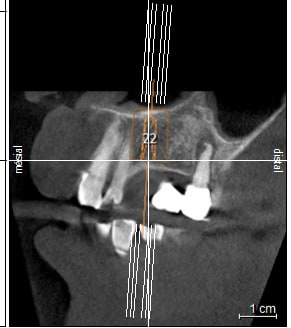

petit cas sympa ancien bridge très mobile....plutôt que d'extraire 25, j'ai déposé la couronne, retraité la dent stabilisation pendant deux mois puis séance d'ostéotension et ce jour pose de deux axioms PX 34120 après expansion...

non, uniquement travail par voie crestale, très légère fêlure niveau 23, mais sans conséquence

en général (99,9% des cas) je ne constate aucune lyse osseusecrestale, ce type de chir. est très douce pour l'os, lame 15, et ostéotomes, pas de forage, pas de consommation d'os, pas d'agression ni de lavage (piezzo), et je fais toujours attention à laisser du sang (sauf pour les photos) ce qui est le meilleur pansement pour l'os.

par contre les axioms doivent être posé en sous crestal, ce qui est fait ici, avec sans doute comme souvent une nécessitè d’ostéotomie, lors de la mise en charge, car il est fréquent que le col implantaire soit recouvert.